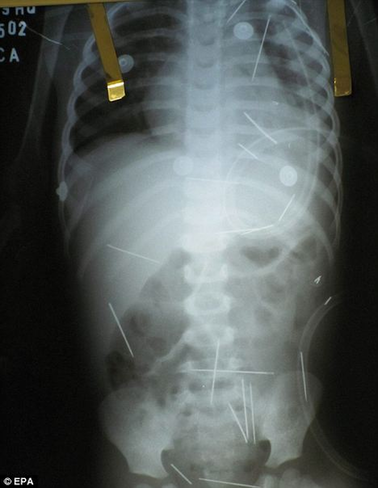

孩子體內(nèi)的一根根縫衣針令人觸目驚心

中國日報(bào)網(wǎng)消息:綜合英美媒體12月16日報(bào)道,日前,巴西東北部巴伊亞州的巴雷拉斯醫(yī)院接診了一名年僅2歲的小男孩,他自稱渾身不適。經(jīng)X光片檢查,醫(yī)生驚異地發(fā)現(xiàn)男童體內(nèi)竟有50根縫衣針。醫(yī)生懷疑,這些針可能是有人惡意扎進(jìn)男孩體內(nèi)。目前警方經(jīng)過初步調(diào)查,已經(jīng)確定男孩的前繼父和另外兩名婦女是本案首要嫌疑人。

主治醫(yī)生路易斯表示,通過X光片看到孩子體內(nèi)竟然有50根縫衣針,他們真是大吃一驚,有好幾根針甚至長達(dá)5厘米,但是孩子身體表面卻看不出任何傷口。路易斯說:“這些針肯定是被人一根一根扎進(jìn)體內(nèi)的。我們在孩子的肺、左腿和胸腔都發(fā)現(xiàn)很多針,根本就不可能是孩子自己吃下去的?!?/p>

據(jù)醫(yī)生介紹,借助手術(shù)他們可以取出一些針,但是有幾根恐怕只能一直呆在男孩體內(nèi)了,因?yàn)樗鼈冸x孩子的重要器官太近,取針反而十分危險(xiǎn);而扎在孩子肺部的那幾根針,也得等到孩子的呼吸穩(wěn)定了之后才能動手術(shù)取出。